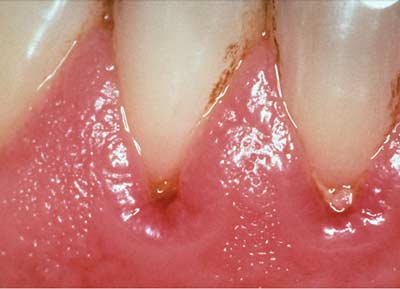

Viêm lợi có 2 dạng chủ yếu:

– Viêm lợi cục bộ: Chứng viêm này không gây quá đau đớn cho người bệnh nhưng rất dễ tái phát.

– Viêm cận răng: ảnh hưởng tới tất cả cấu trúc bảo vệ răng. Loại viêm này lan rộng và ăn sâu vào trong lợi khiến người bệnh đau đớn. Tuy nhiên một khi bệnh được chữa khỏi, khả năng tái phát là rất ít.